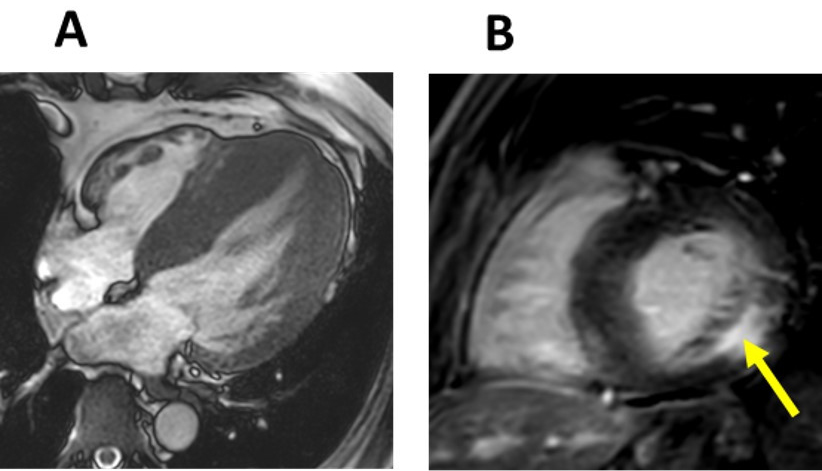

Fig. 7.Late stage Fabry disease. (A) Four-chamber cardiac magnetic resonance (CMR) image of a patient with late stage Fabry disease showing severe concentric left ventricular hypertrophy. (B) Short-axis late gadolinium enhancement (LGE) CMR image demonstrating extensive LGE in the basal inferolateral wall (arrow).

This is the most advanced cardiomyopathy phase and is characterized by replacement fibrosis recognized by the presence of LGE in CMR imaging. LGE extends beyond the BILW towards other basal and mid-myocardial segments of the LV and could cause wall thinning in the BILW.

The existence of focal fibrosis (irreversible) can be assessed by the presence and distribution of the LGE following the administration of contrast agents. The typical distribution of LGE in FD patients is in the mid myocardium layers of the BILW, the same region that has been reported to be the first to present mechanical dysfunction [83]. Why this region is affected in FD remains unknown. An ischemic etiology is unlikely since ischemic necrosis usually starts at the sub-endocardium. One hypothesis is increased local wall stress in the BILW since LV work load is highest in this region [55, 84]. The BILW is the most mobile of the basal segments and likely faces the most junctional stress transmitted from the fibrous skeleton into the myocardium [85]. Another explanation could be a higher sphingolipid deposition and inflammatory response in the aforementioned segments. Atypical patterns of LGE in the mid and apical LV have also been reported in the literature [85]. Curiously, patients with non-concentric LV hypertrophy (such as asymmetric septal hypertrophy that mimics HCM) had more total and atypical distribution of LGE [85].